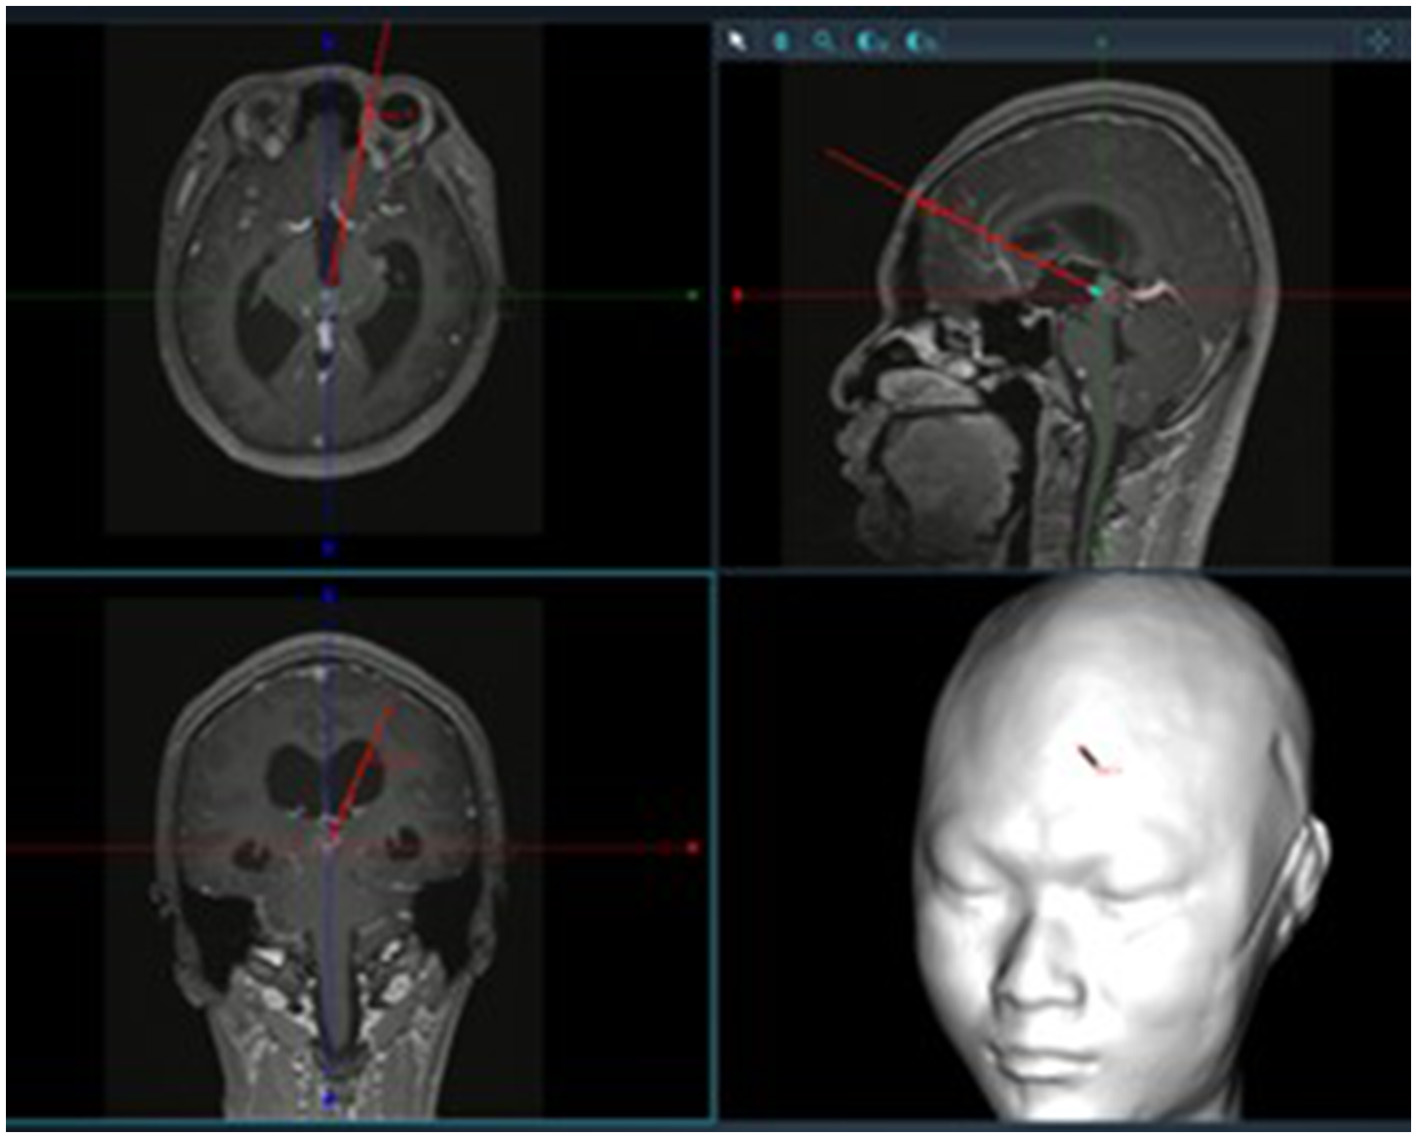

Patients were positioned supine with the head elevated 15°, fixed using a Mayfield head frame under general anesthesia. Burr hole locations were planned using the Huake Precision Neurosurgery Robot: (1) The trajectory for tumor resection was determined by projecting the line connecting the foramen of Monro and the anterior tumor margin to the frontal bone surface. (2) The burr hole for third ventricular floor fenestration was planned along the line from the foramen of Monro to the infundibular recess (Figures 1, 2). A right semi-coronal incision was made, and holes drilled under robotic navigation.

Figure 1

Surgical trajectory planning using neuronavigation.

Figure 2

Localization of bone openings for tumor resection and third ventriculostomy (typically ~2.5 cm lateral to midline and ~5.2 cm above the eyebrow ridge for tumor resection; ~2.5 cm lateral and ~10.0 cm above the eyebrow ridge for ventriculostomy).